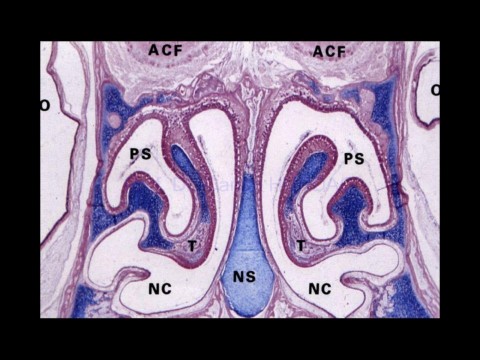

Page 11 - Solunum Sistemi

02-Dec-20                                     Solunum sistemi histolojisi,                                                 11